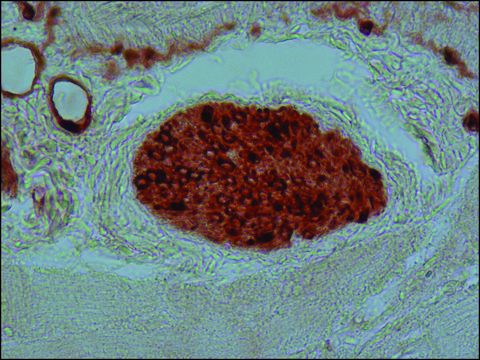

immunohistochemistry: 1.5-3  μg/mL using immunoperoxidase labeling of pronase digested, formalin-fixed, paraffin-embedded sections of rabbit tongue.

Monoclonal Anti-S-100 (β-subunit) (mouse IgG1 isotype) is derived from the SH-B1 hybridoma produced by the fusion of mouse myeloma cells and splenocytes from an immunized mouse. S-100 is a set of small, thermolabile, highly acidic homo or hetero-dimer calcium binding proteins. The protein exists in two isoforms namely, S-100α and S-100β, which are brain specific.

S-100β is a calcium binding protein. It is mainly present in astrocytes and neurons of hindbrain and spinal cord.

Purified bovine brain S-100β